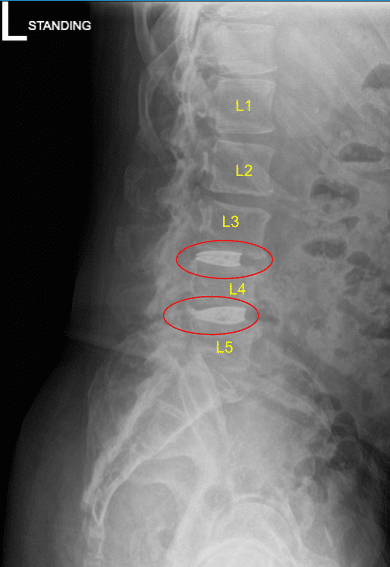

MRI and CT of his lumbar spine demonstrated severe degenerative disc space breakdown at L3-L4 and L4-L5 and accordingly they were offered a surgery for discogenic pain. The risks and potential benefits of surgery were extensively explained to the patient.

Disc space narrowing at L3-L4 and L4-L5

They signed informed consent and were brought to the operating room for the aforementioned procedure. The findings of the preoperative lumbar spine x-ray are shown above and the patients also had a preoperative computerized tomography scan (CT scan) shown above.